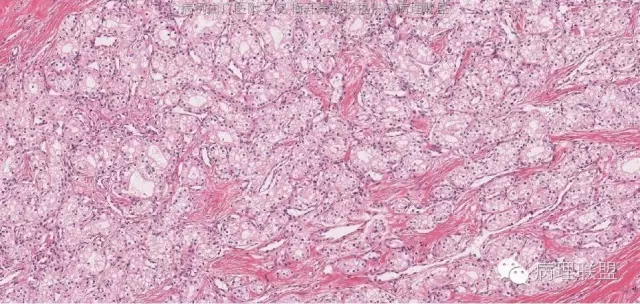

肿物与正常胰腺组织分界清楚,肿瘤组织被纤维组织分隔成巢状。

肿瘤细胞排列成腺管状或腺泡状,腺管或腺泡排列紧密,背靠背。瘤细胞形态与浆液性囊腺瘤的瘤细胞形态完全一致。因此,诊断为浆液性囊腺瘤,实体型。